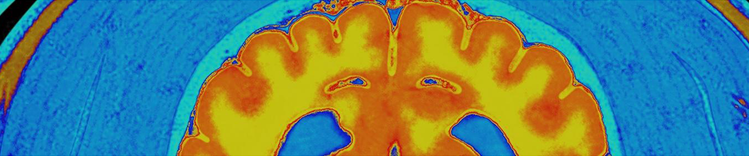

IRM CÉRÉBRALE

Changements dans le cerveau vieillissant

Les changements physiques du cerveau qui sont associés au vieillissement comprennent :

- Atrophie (rétrécissement) des tissus de certaines régions

- Augmentation du volume ventriculaire

- Perte des neurones et des synapses et diminution de la formation de nouveaux neurones

- Accumulation anormale de protéines